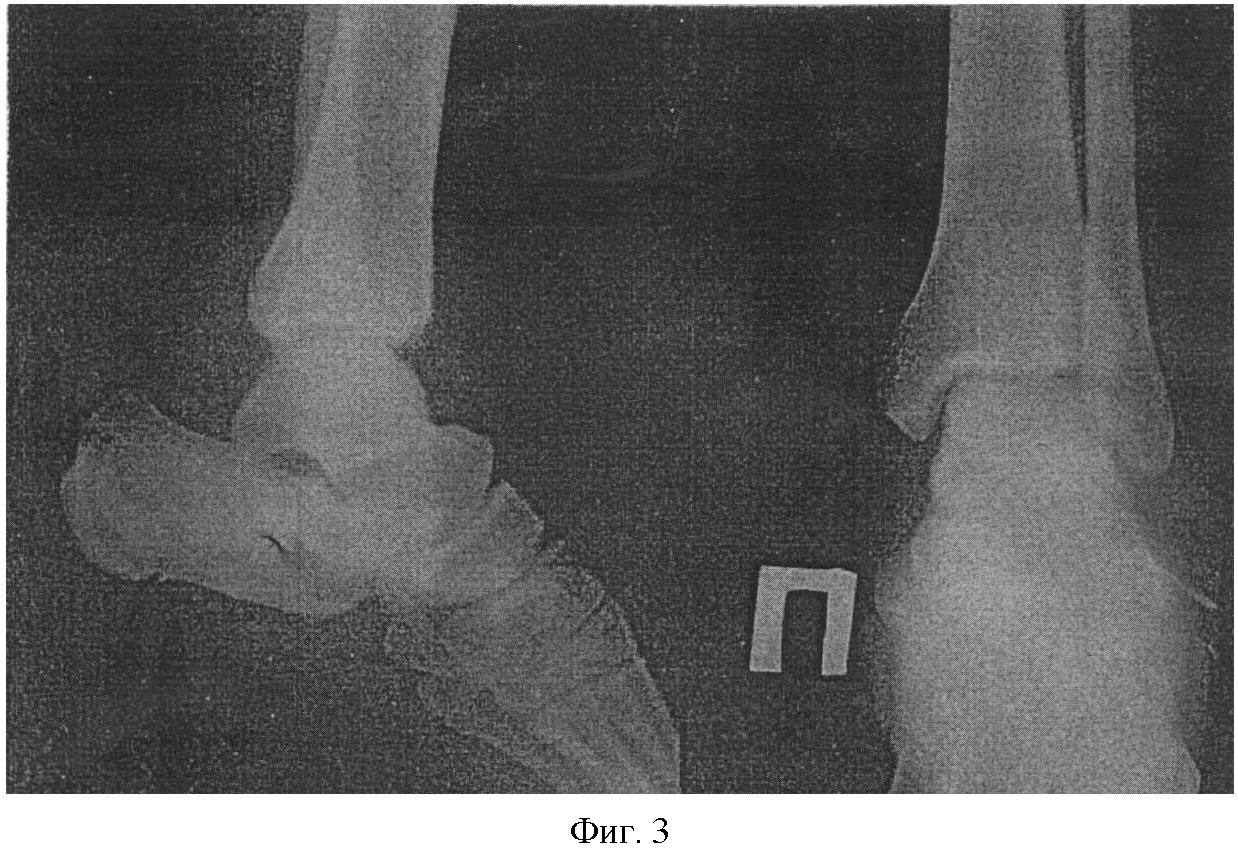

Способ поясняется иллюстрациями, где на фиг.1 показана компоновка компрессионно-дистракционного аппарата внешней фиксации; на фиг.2 показана схема проведения вспомогательных спиц через пяточную кость с большим смещением отломка (вид сбоку); на фиг.3-6 приведены рентгенограммы, иллюстрирующие клинический пример: на фиг.3 дана травмированная стопа до операции; на фиг.4 – снимок этапа 0репозиции; на фиг.5, 6 – окончательная репозиция.

Б-ная С-ва, 1987 г.р., находилась на лечении в НИЦТ «ВТО» с 15.12.08 г. по 9.12.08 г.

Диагноз: Закрытый оскольчатый перелом правой пяточной кости суточной давности (фиг.4).

Операция 5.12.08 г.: Закрытый чрескостный остеосинтез перелома правой пяточной кости (фиг.3). Больной установлен аппарат Илизарова по схеме, приведенной на фиг.1, проведены вспомогательные спицы (по схеме фиг.2), с помощью которых осуществлена репозиция перелома с восстановлением формы пятки (фиг.4-6). Больная выписана на амбулаторное лечение с фиксаций в аппарате на срок 3 месяца, с последующим рентген-контролем и демонтажом.